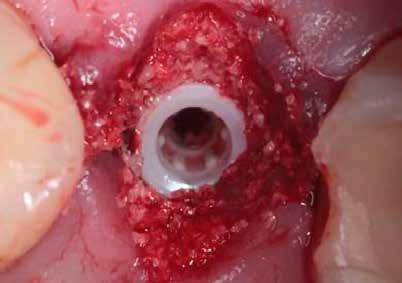

3. a–b ábrák: Fogeltávolítást követő alveolus prezerváció. – 4. a–b ábrák: Az implantátumok beültetése.

5. a–b ábrák: A behelyezett implantátumok okkluzális nézetből. – 6. ábra: Az implantátum és a csontpótló anyag.

A fogak eltávolítása minimálinvazív módon történt, amelynek során a parodontális rostokat egy periotom segítségével átvágtuk, így lebenyes feltárásra nem volt szükség (3. a–b ábrák) . Az implantátumokat a frissen eltávolított fogak alveolusaiba ültettük be. A foghúzást követően minden alveolust alaposan ellenőriztünk az endodontiai, vagy parodontális eredetű gyulladásos szövetmaradványok eltávolítása érdekében, majd fiziológiás sóoldattal bőségesen átöblítettük. Megfelelő előfúrást követően a kerámiaimplantátumokat 30 fordulat/perc sebességgel és 35 Ncm behajtási nyomatékkal helyeztük be (4. a–b ábrák) . A réseket csontpótlóval töltöttük ki (Maxresorb ® 0,5–1,0 mm szemcseméret, 0,5 cm 3 térfogat, Straumann ®; 6. ábra ).